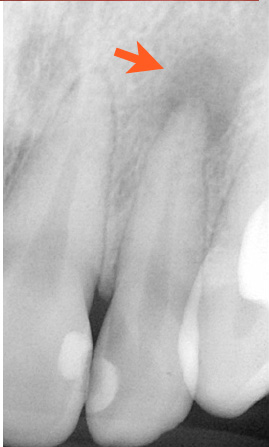

右の写真は矢印のところで強く当たっていました。その結

果、いつの間にか神経が死んで、根の先に病巣ができていま

す。幸い、痛みは自覚していませんでした。虫歯が原因であろ

うが、噛み合わせが原因であろうが、痛みは同じです。両方とも神経を取れ